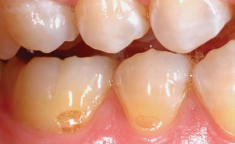

Buccal Bifurcation Cyst | 36, 46 Buccal (兩側 1/3) | 5-13y | - |

![]() |